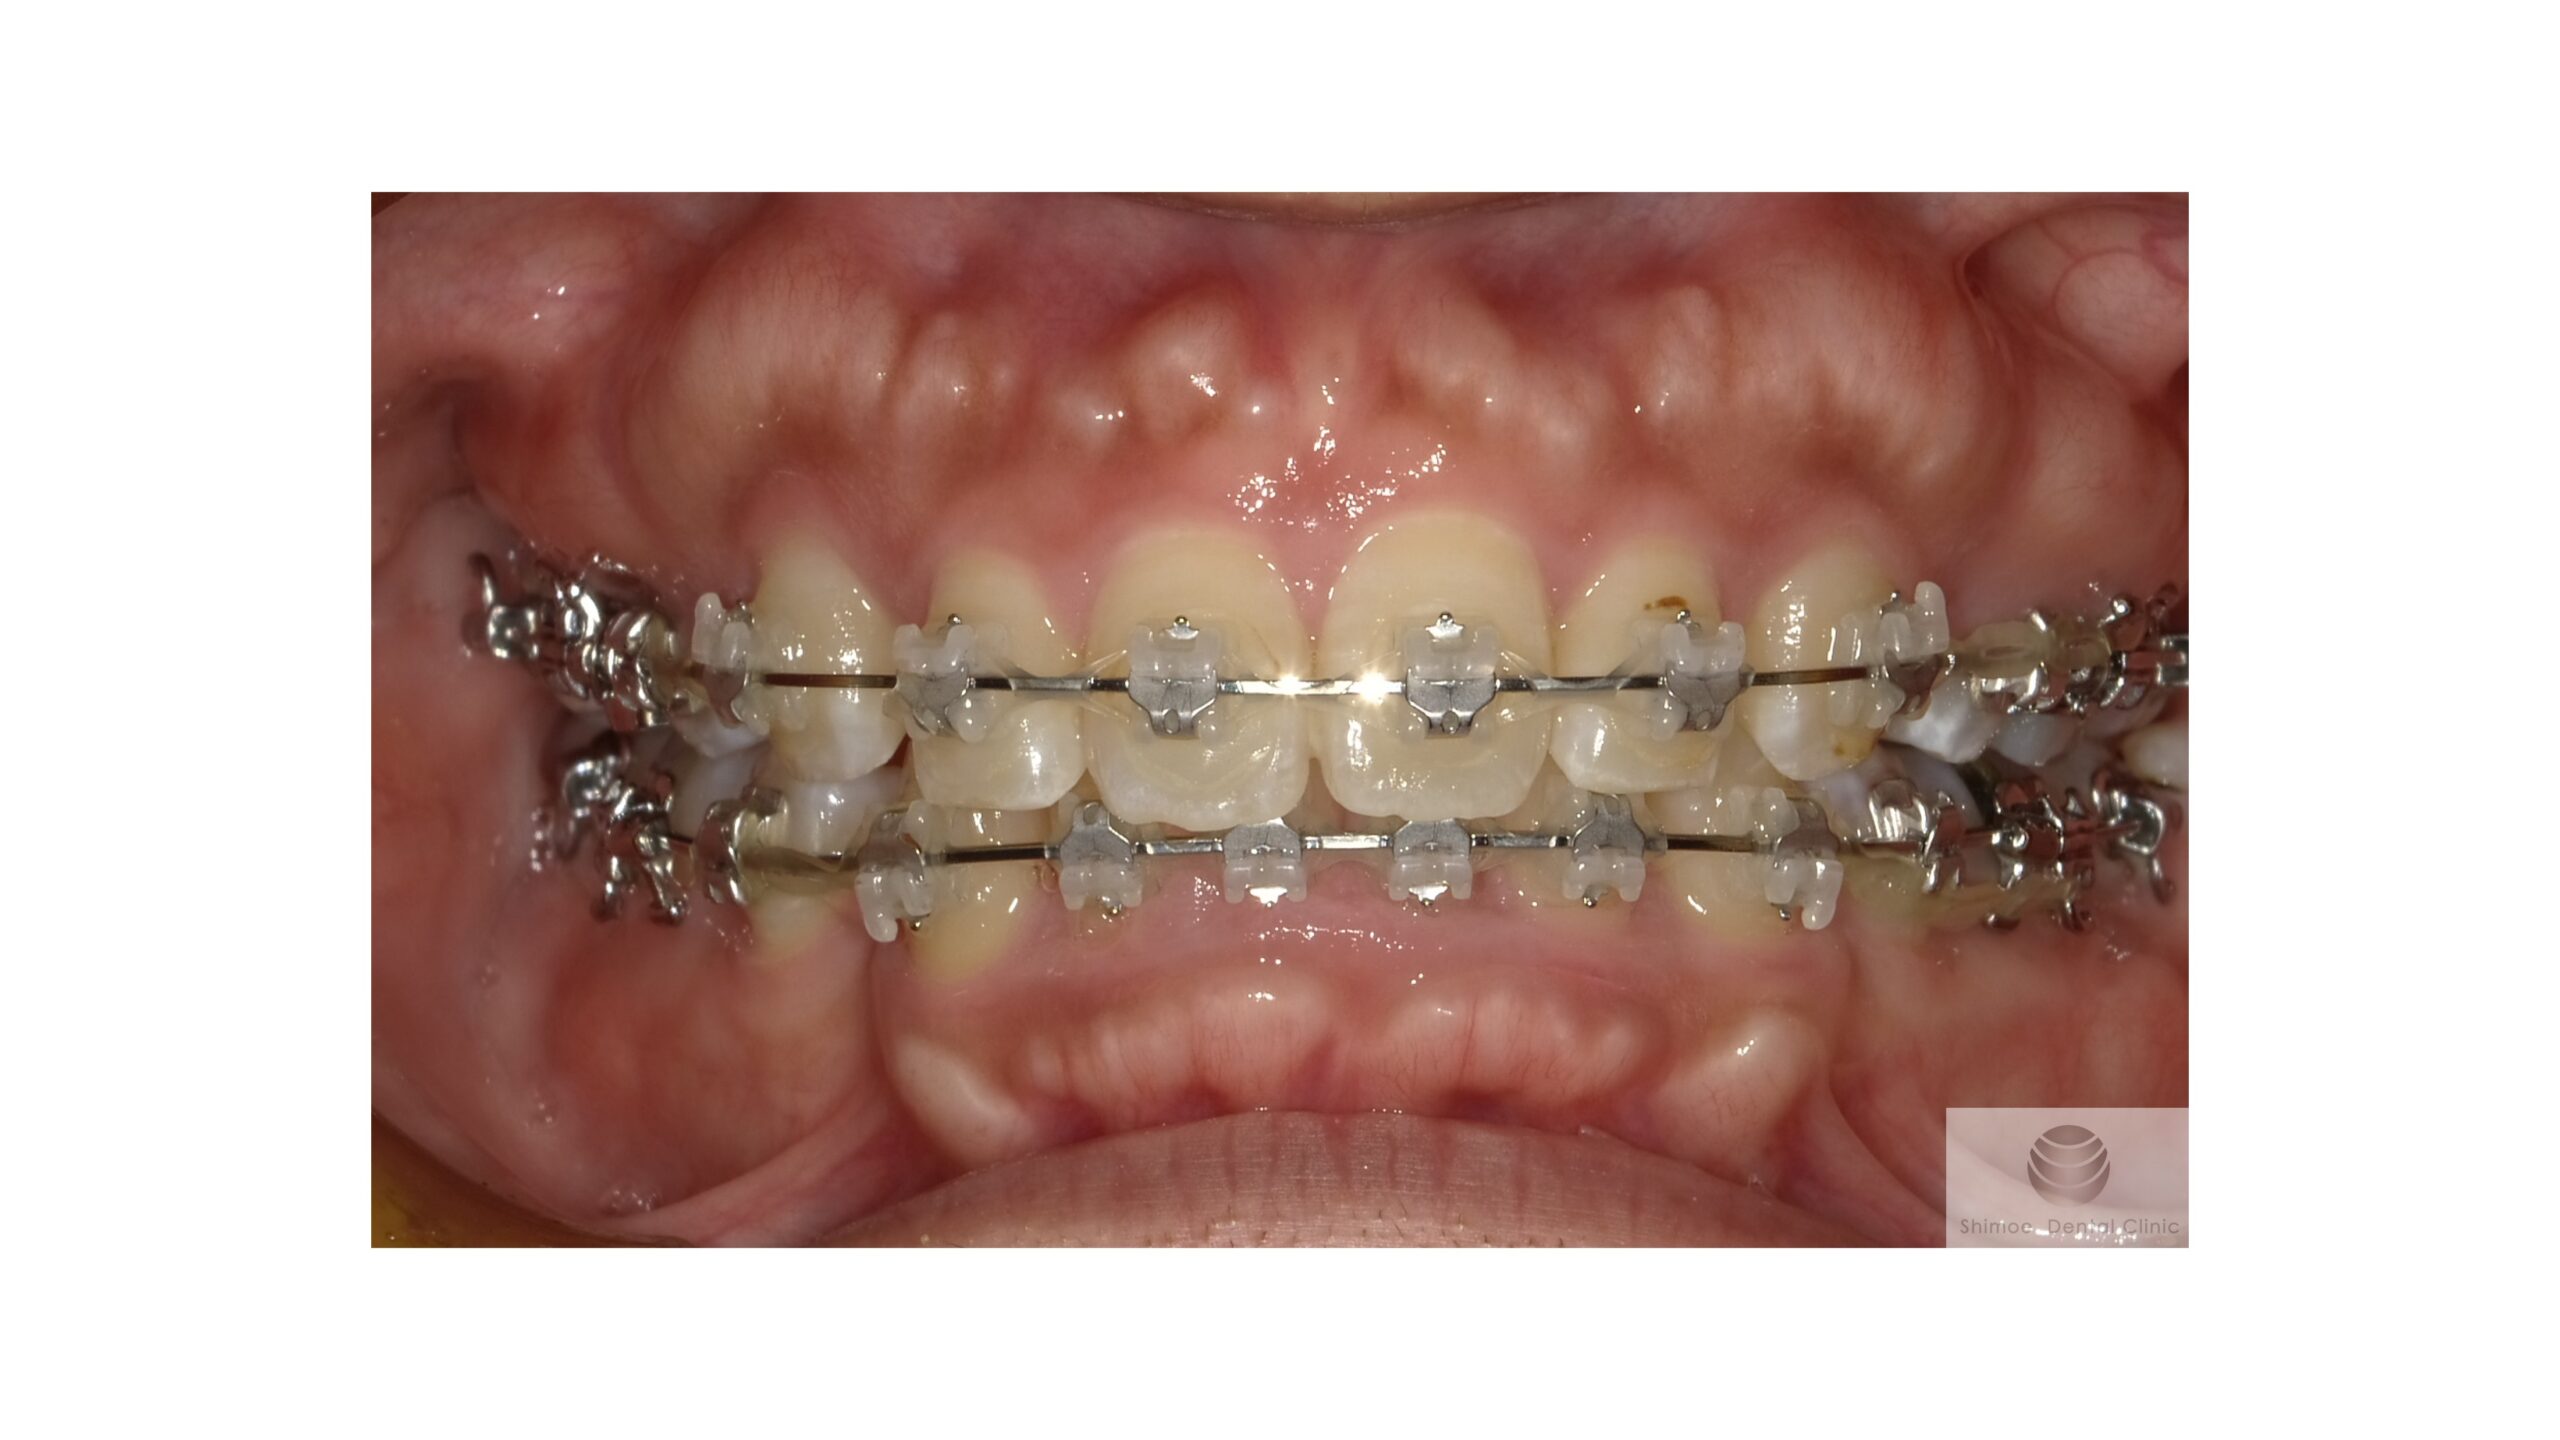

矯正中

他院での矯正中 口腔内写真

上下の前歯部を中心に、矯正によって歯が動いたことで、唇側の骨が添加して骨隆起の凸凹が大きくなっています。

骨隆起は矯正によって必ず大きくなるものではありません。骨質など個々の条件によって、できやすい方がいらっしゃるようです。

装置が外れるまで待ちます。